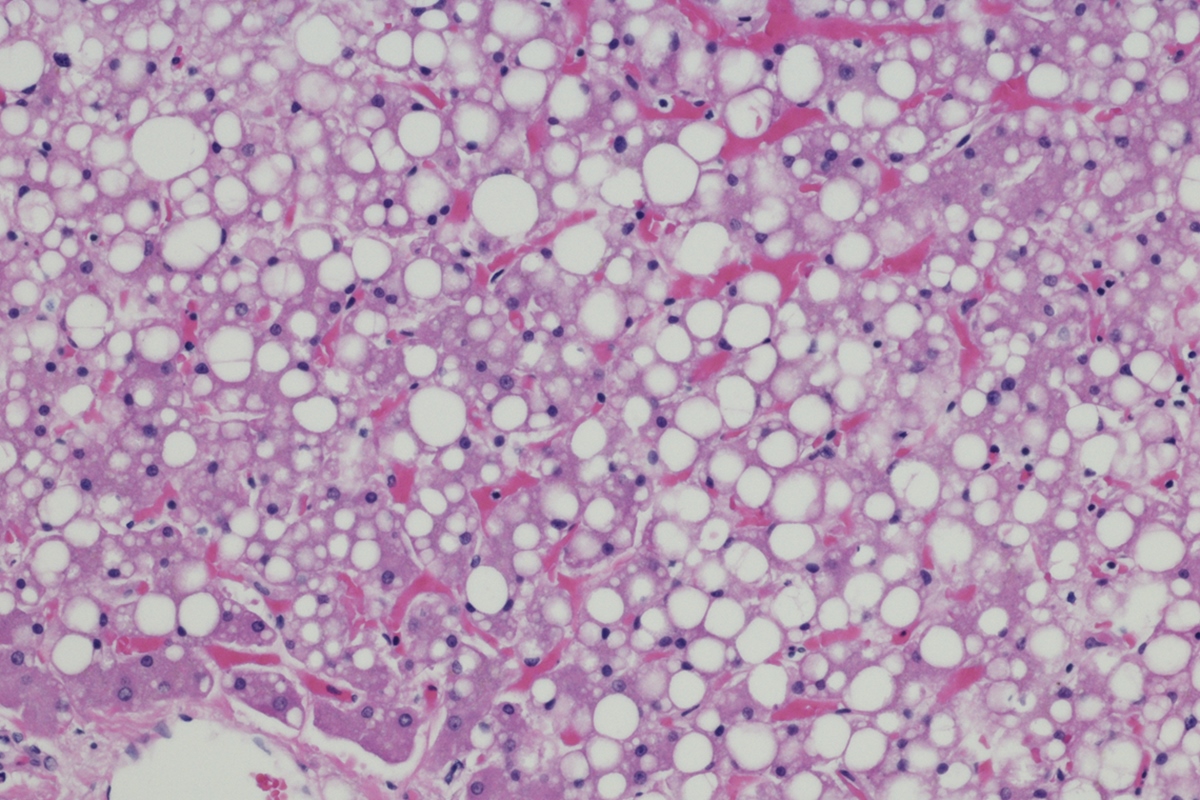

Obesidade: estudo redefine conhecimento sobre metabolismo de gorduras

Pesquisadores da Universidade de Toulouse, na França, identificaram uma relação entre a obesidade e um distúrbio que causa o efeito oposto, a perda de gordura compulsória da lipodistrofia.

Eles analisaram a proteína HSL e identificaram nela uma ação para além da quebra de gordura. O estudo publicado na Cell Metabolism no domingo (23/11) indica que a proteína também atua no núcleo das células de gordura, os adipócitos, regulando a expansão do tecido adiposo.

Anteriormente, os médicos acreditavam que a proteína HSL, por incentivar a quebra de gordura para abastecer o corpo em momentos de alta adrenalina, podia também se tornar uma espécie de interruptor do processo de uso de gordura e que sua retirada levaria necessariamente à obesidade.

Ao testarem retirar a proteína do organismo de camundongos, eles descobriram que, na realidade, os animais desenvolveram o distúrbio contrário, a lipodistrofia. A condição é marcada por perda de massa gorda e leva a riscos de distúrbios metabólicos tão graves quanto a obesidade.

Ação da proteína que queima gordura

A equipe investigava inicialmente a localização correta da proteína e descobriu que ela aparece em gotículas lipídicas e também no núcleo de adipócitos. Nesse ambiente, a HSL interage com outras moléculas e colabora com mecanismos de manutenção do tecido adiposo.

“A HSL é conhecida desde a década de 1960 como uma enzima mobilizadora de gordura. Mas agora sabemos que ela também desempenha um papel essencial no núcleo dos adipócitos, onde ajuda a manter o tecido adiposo saudável”, afirma o médico Dominique Langin, líder do estudo.

O processo descoberto por eles revela que a adrenalina ativa a HSL e estimula a saída da proteína do núcleo das células de gordura durante períodos de jejum. Em camundongos obesos, há uma concentração no núcleo, como se as proteínas lá presas não pudessem iniciar o processo de queima de gordura.

Implicações para além da obesidade

Por isso, regular a obesidade e a lipodistrofia não é tão simples quanto adicionar ou retirar o HSL da equação. É o movimento dela na célula que forma a regulação correta da gordura corporal.

Os resultados apontam que adipócitos defeituosos resultam tanto em obesidade quanto em lipodistrofia. As duas condições provocam falhas de regulação metabólica e ampliam o risco cardiovascular, mostrando como um quadro aparentemente oposto de saúde pode compartilhar tanto origem como riscos.